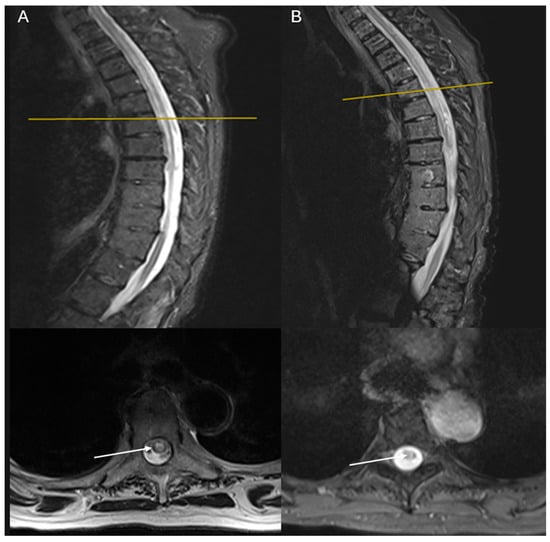

| Level | T3–T8 | T3–T8 | C3–C7 | C4–C7, T10–T12 |

| EDSS | 7.5 | 7.5 | 7 | 4 |

| Outcome | Stagnant—bedridden | Improved—able to stand and walk with support and self-service capability | ||